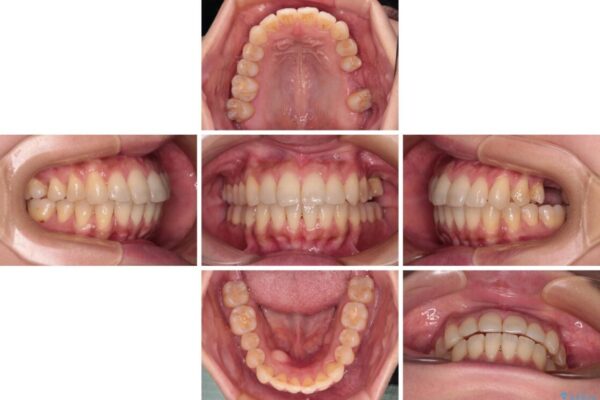

治療前

• インビザラインによる矯正治療と奥歯のインプラント治療 治療前画像